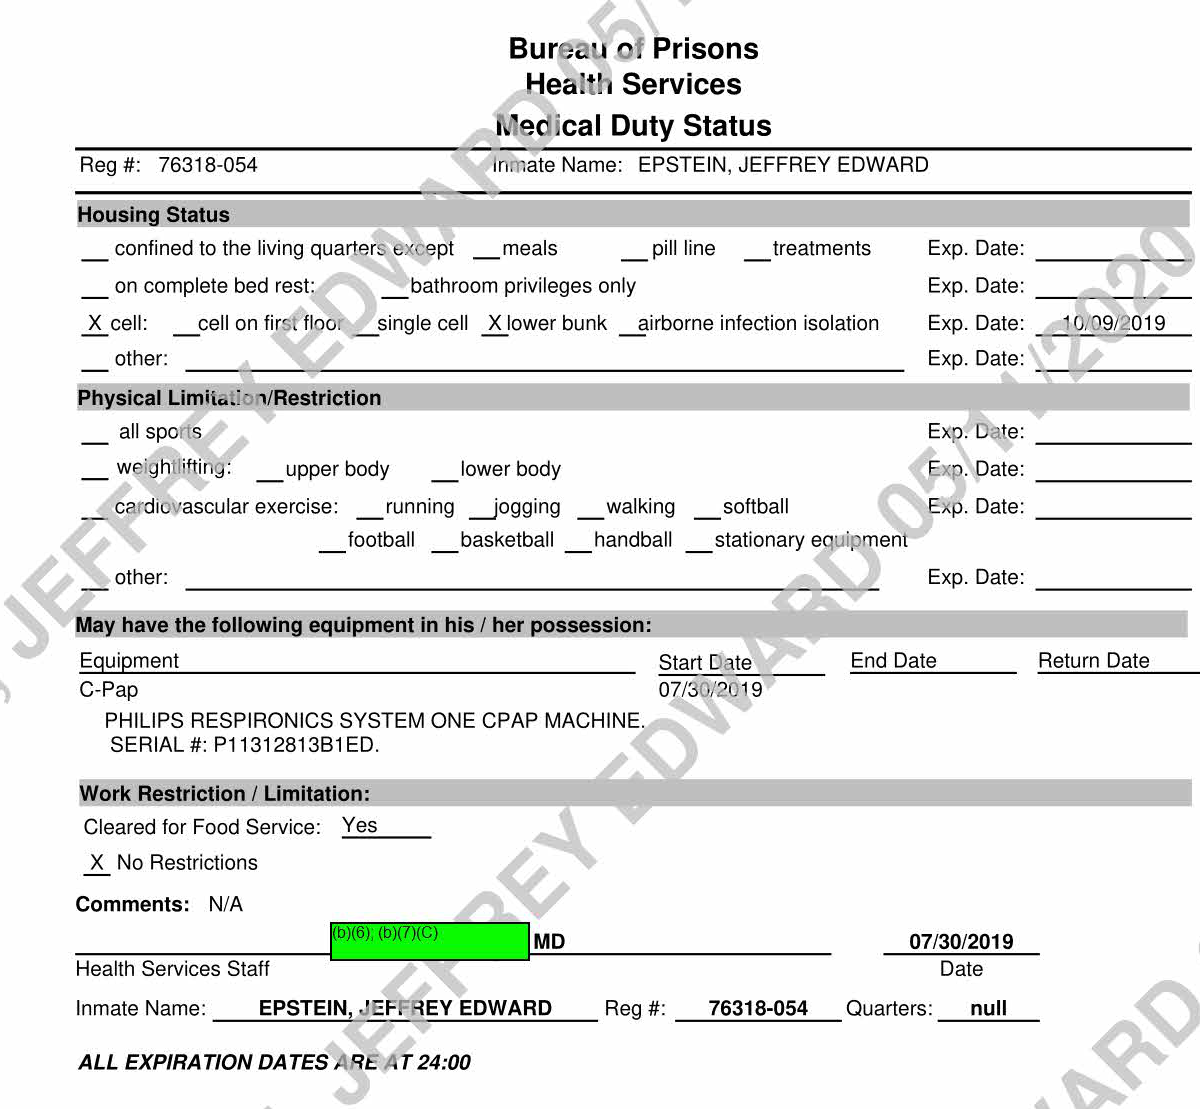

Fwd: Jeffrey Epstein, 76318-054 From b)(6); (b)(7)(C) To Executive Stafff._b_X5_>;_<b_X7_><_c> ______ __. Date Subject: Attachments: Good morning all, b)(6); (b)(7)(C) 2019/07/26 10:10 Fwd: Jeffrey Epstein, 7 6318-054 TEXT.htm Epstein's attorneys are trying to get him his CPAP machine per our request. Can we have them hand-deliver it to medical staff as we have in previous instances? Thank ou, b)(6); (b)(7)(C) > > ~ b)(6); (b)(7)(C) Mr. }~i~,., I l@gmail.com> 7/26/2019 9:50 AM > > > Is Mr. Epstein approved to receive a CPAP machine? If so, should we send it directly to him through the inmate mail system? Please confirm. Thank you. b)(6); (b)(7)(C) Page 747